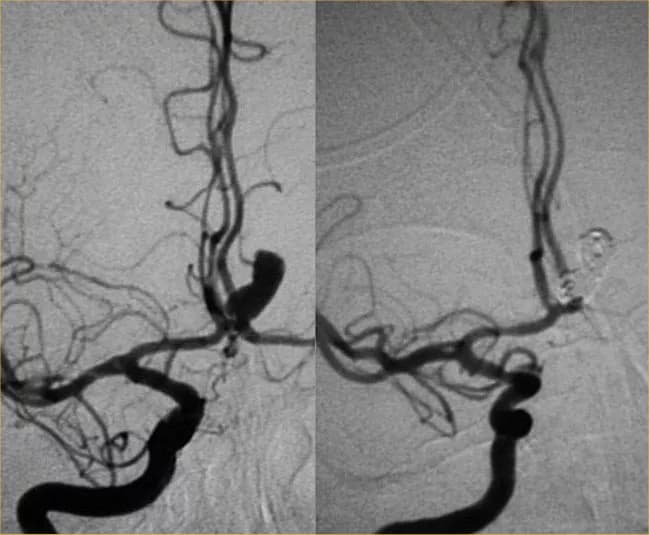

• The Embolization of Brain Aneurysm procedure involves placing soft metal coils within the aneurysm to stop a potential rupture

• Coils are inserted through the catheter and placed within the aneurysm. The body starts healing around the coil and blood flow into the aneurysm is blocked, thus preventing its rupture

• Once the catheter is on the target site, detachable coils are inserted and placed in the aneurysm